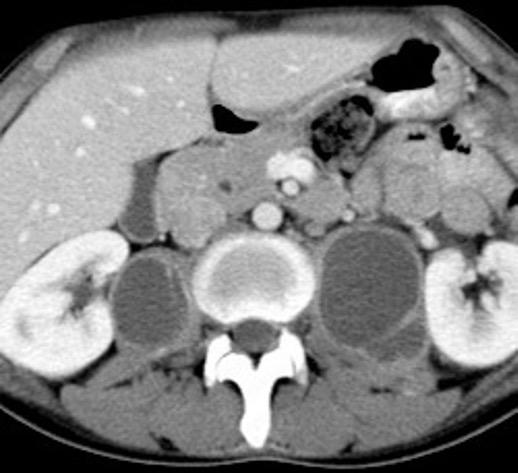

Ganglios retroperitoneales (flechas negras)

germinales del testículo izquierdo Nódulos pulmonares múltiples. (flechas verdes). Ganglios paratraqueales. (flechas amarillas). Dudoso ensanchamiento retrocrural (flechas negras)

Panda A et al. “Straddling Across Boundaries”. Thoracoabdominal Lesions: Spectrum and Pattern Approach. Curr Probl Diagn Radiol, 2015